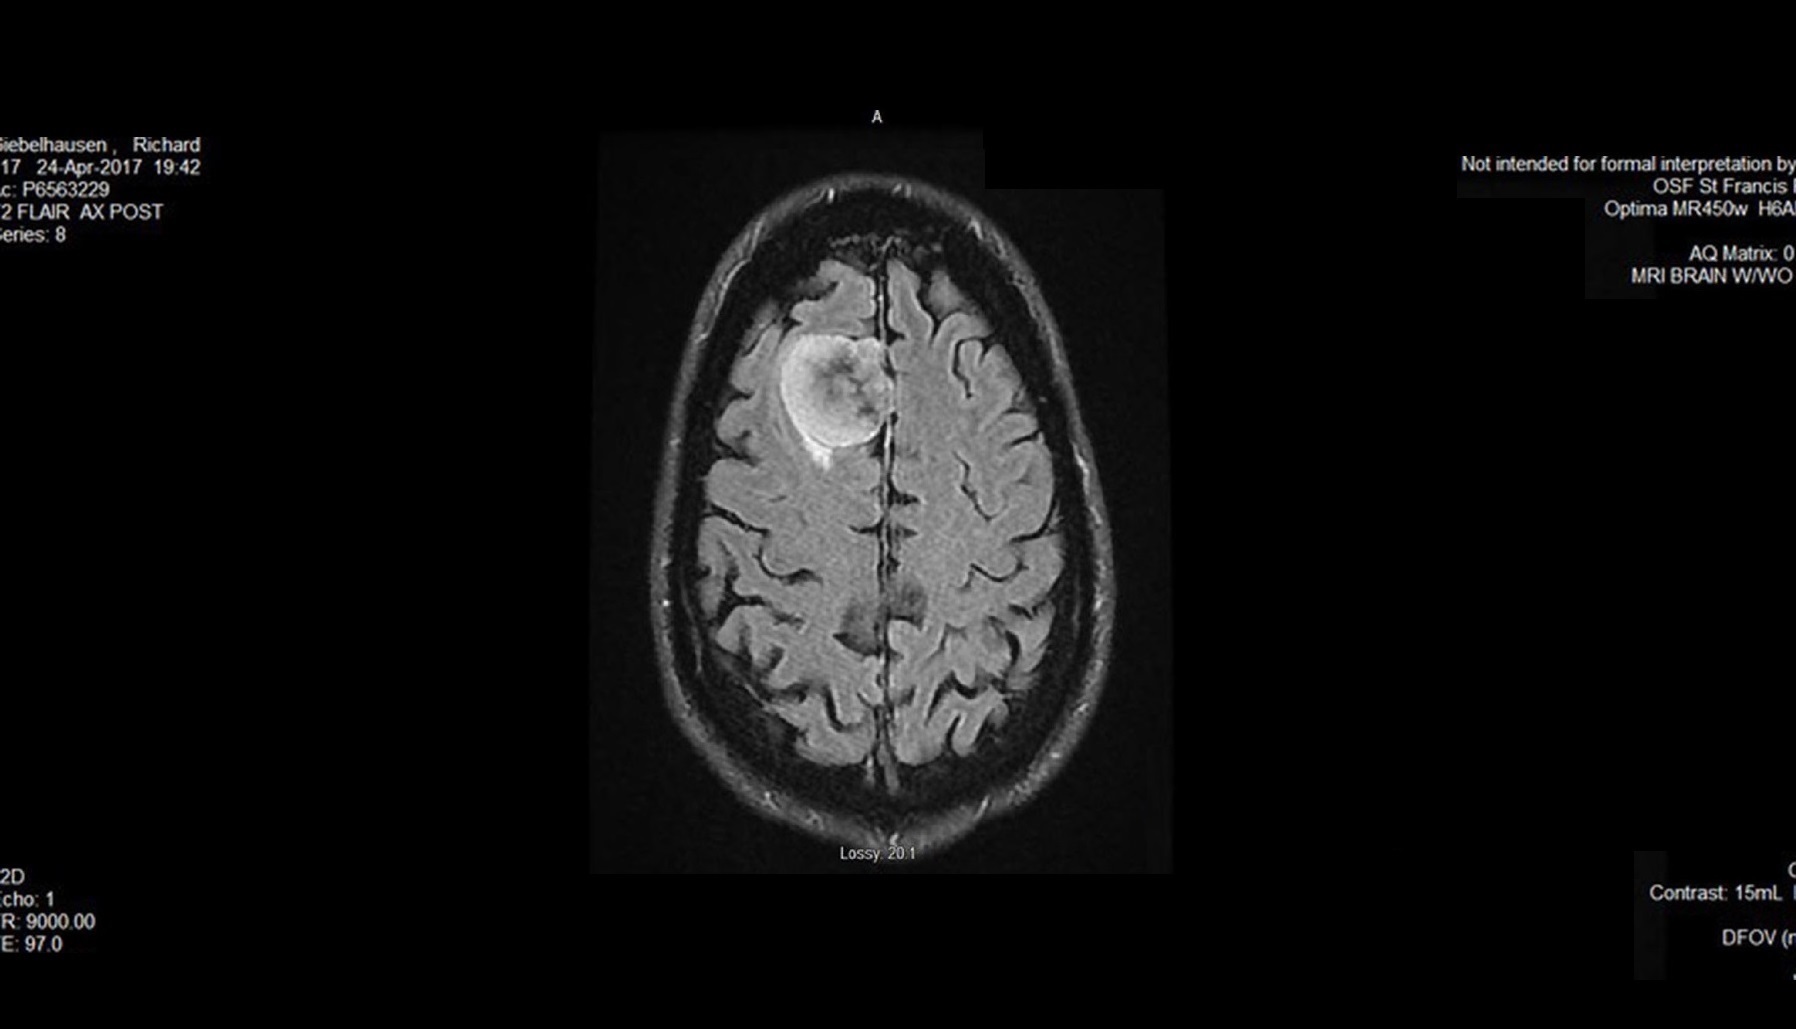

When the neurologist showed us the CT scan, he pointed out what he said appeared to be a meningioma – a type of brain tumor that is usually benign. We were somewhat relieved, but still scared to think this had been growing in my brain.

He told us meningioma are usually very slow-growing, and in most cases are discovered accidentally – like mine. He said in some cases doctors just monitor them, and in other cases they’re removed.

When I met with the neurosurgeons at OSF HealthCare Illinois Neurological Institute to discuss what approach we would take, I met with Sarah Beam, an advanced practice nurse, and Dr. Andrew Tsung, a neurologist who specializes in brain tumor. They told me my tumor – about the size of a plum – needed to come out.

They also told us this type of tumor is very slow-growing, and I had most likely had it for decades.

Part of it was the standard pre-surgical prep, but I also needed to have another MRI. They put some small “Cheerios” on my head to serve as GPS markers for the surgeon during the procedure. After the MRI, Sarah stopped by to tell me a little more about what was going to happen.

I was blown away by the surgical suite. I had been in operating rooms before, but this was something else. On one wall alone were five big-screen monitors. I even recognized Timmy on two of them.